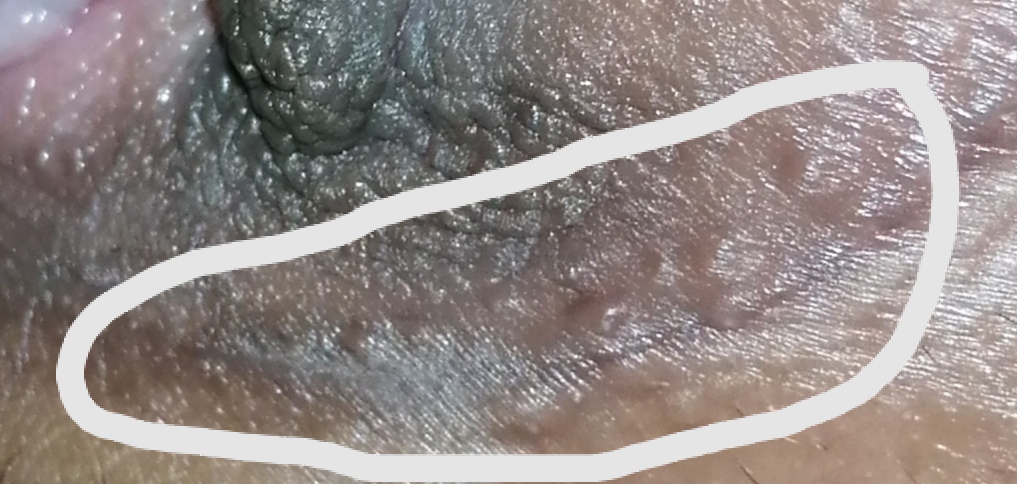

เป็น​ตุ่มบริเวณ​แคมใหญ่แบบนี้มีโอกาส​เป็น​อะไรได้บ้างคะ​ เริ่มเป็นตอนช่วงใกล้เป็นประจำเดือนครั้งแรกแล้วตกขาวมาเยอะมาก​หลังจากนั้นก็เป็นตามรูปเลยค่ะ​ มีอาการคันแต่ไม่มาก​เป็นบางครั้ง

อายุ: 15 ปี เพศ: F น้ำหนัก: 46 กก. ส่วนสูง: 165ซม. ดัชนีมวลกาย : 16.90 (ค่ามาตรฐานคนเอเชีย=18.5-22.9)

จากอาการตุ่มขึ้นบริเวณแคมใหญ่ เริ่มเป็นช่วงใกล้มีประจำเดือน และมีตกขาวร่วมด้วย โดยมีอาการคันเล็กน้อยเป็นบางครั้ง เบื้องต้นจากลักษณะรุป ยังไม่พบลักษณะชัดเจนที่บ่งบอกถึงโรคติดต่อทางเพศสัมพันธ์ครับ อาการที่เป็น อาจคล้ายผิวหนังอักเสบจากการระคายเคืองหรือเสียดสี รวมถึงอาจเกิดจากความชื้นหรือฮอร์โมนช่วงก่อนมีประจำเดือนก็ได้ครับ แต่เพื่อความชัดเจนและสบายใจ แนะนำให้มาตรวจเพิ่มเติมกับแพทย์โดยตรง เพื่อดูลักษณะของตุ่ม ตรวจตกขาว (หากยังมีตกขาวผิดปกติ) และประเมินว่าจำเป็นต้องรักษาหรือไม่ครับ